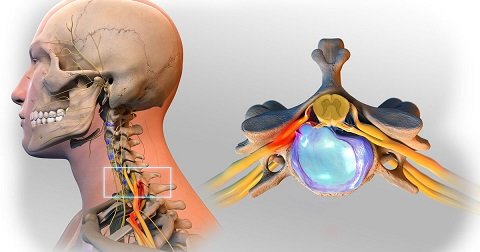

3- هرنی دیسک

یا دررفتن دیسک . در این وضعیت قسمت حلقوی محیطی دیسک (آنولوس فیبروزوس) پاره شده و قسمت مرکزی (نوکلئوس پولپوزوس) از بین شکاف پارگی به بیرون راه پیدا میکند. این قسمت بیرون زده را هرنی یا فتق میگویند. مهمترین مشکلی که در فتق دیسک بوجود میاید اینست که قسمت بیرون زده به اعصابی که در حال بیرون آمدن از نخاع و مهره هستند فشار آورده و همین فشار موجب بروز بسیاری مشکلات از جمله درد اندام فوقانی است .